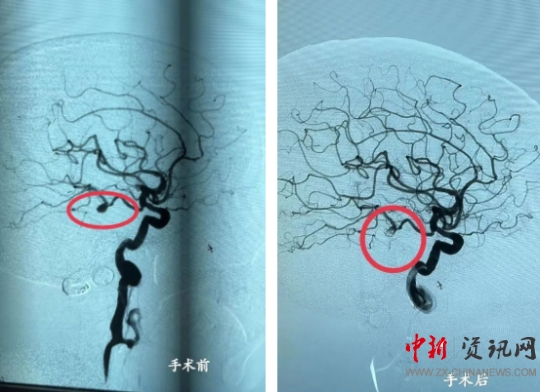

中新河南網(wǎng)駐馬店6月7日電(通訊員:于紅松)6月1日,上蔡縣人民醫(yī)院神經(jīng)內(nèi)科一病區(qū)與麻醉科、導管室緊密配合,順利完成一例“DSA下全腦血管造影+腦動脈瘤彈簧圈栓塞術(shù)”,手術(shù)的成功開展標志著上蔡縣人民醫(yī)院在腦血管介入治療上有了突破性的進展。

16:25,徐濤主任和張文杰副主任在上級醫(yī)院專家指導下,為患者行腦動脈瘤栓塞術(shù)。手術(shù)過程順利,術(shù)后患者病情平穩(wěn),造影復查顯示:動脈瘤栓塞致密,遠端血管正常,家屬對診療結(jié)果非常滿意。